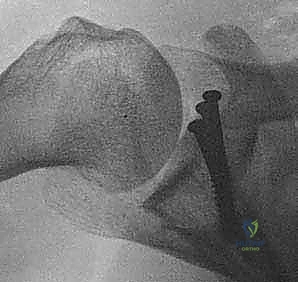

الخطوة 6: زراعة وتثبيت الطعم العظمي

يتم